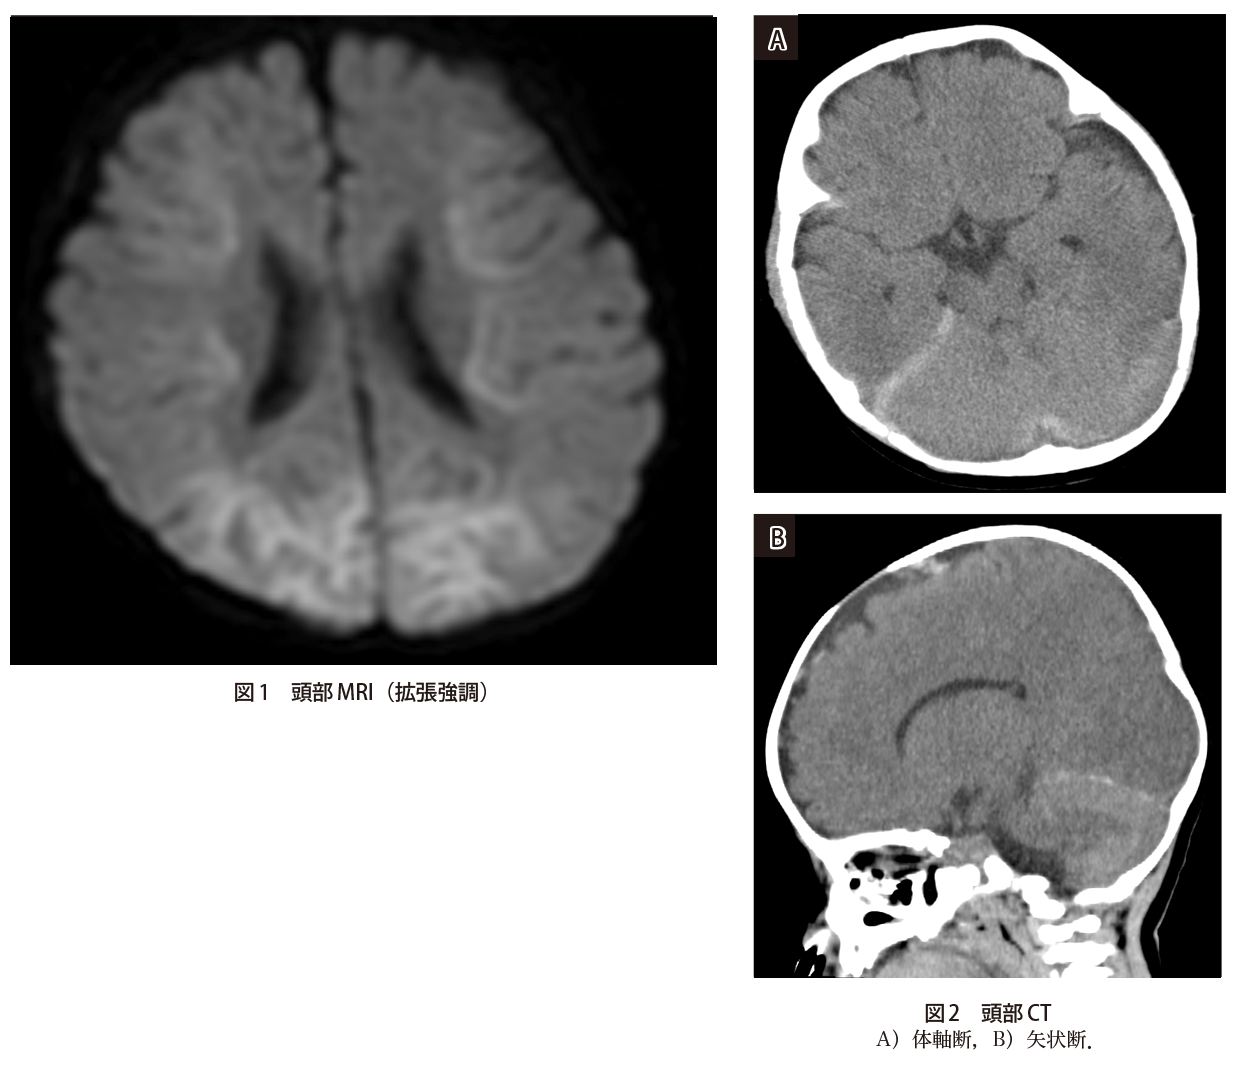

けいれん 意識障害で搬送された5カ月女児 実践 画像診断q A 羊土社 レジデントノート 羊土社